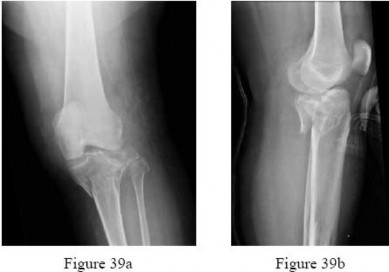

Question 28

A 35-year-old skier sustains a Schatzker Type II (split-depression) tibial plateau fracture after a fall. Which of the following intra-articular structures is most frequently injured in conjunction with this specific fracture pattern?

Explanation

Schatzker Type II fractures involve a split-depression of the lateral tibial plateau. Associated soft tissue injuries are extremely common in tibial plateau fractures. The lateral meniscus is torn or entrapped in the fracture site in up to 40-50% of lateral plateau fractures (Schatzker I and II), making it the most frequently injured structure in this context.